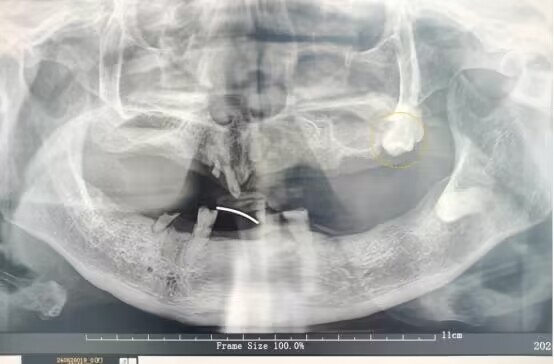

王婆婆口腔影像图

半个多月前,家住武汉的王婆婆感觉口腔内脓肿疼痛。老人自以为是上火了,并未在意。在家拖了一周后,肿痛反而越来越严重,王婆婆这才来到武汉市第四医院口腔科就诊。接诊的口腔科主任向国林详细检查了王婆婆的情况,发现她左侧上颌腭部严重红肿化脓,组织肿胀已经影响到患者进食和呼吸。引起王婆婆严重感染的罪魁祸首竟然是一颗埋伏阻生智齿。

向国林介绍,智齿一般在16岁到25岁萌出,但是部分智齿受邻牙、牙槽骨或软组织的影响,可能无法长出来,成为埋伏阻生智齿。“完全埋伏阻生的智齿在牙龈表面完全看不见,易被误认为没有长智齿,只有通过拍片才能发现。”向国林解释,导致王婆婆口腔感染的就是这样一颗埋伏在牙槽骨中的智齿。等到患者高龄,牙槽骨吸收萎缩、身体免疫力下降,口腔细菌进入牙齿周围就引发了炎症,由于没有及时治疗,患者的感染逐渐加重,引起周围组织肿胀化脓。